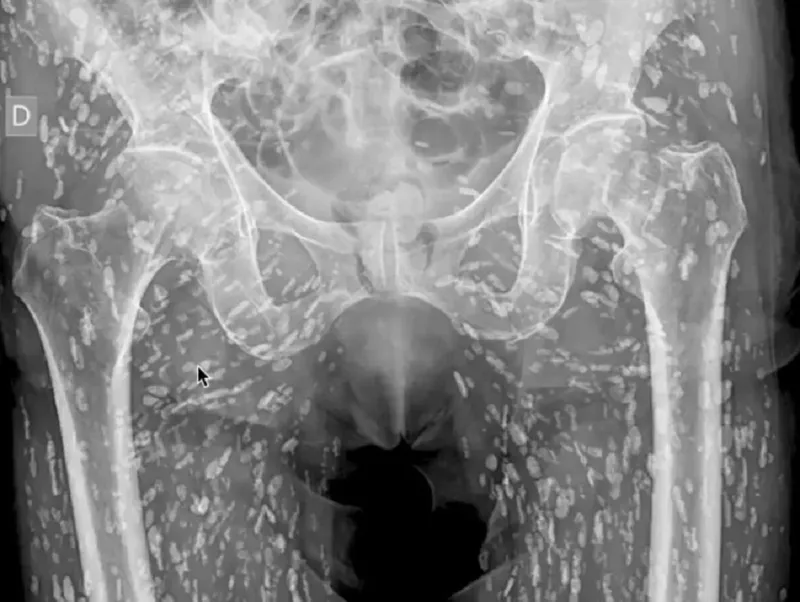

Sam Ghali, medic de urgență specializat în urgențe cardiovasculare și radiologie de urgență la Clinică medicală din Jacksonville, Florida, a împărtășit recent o radiografie neobișnuită a zonei pelvine a unui pacient care arăta corpul acestuia plin de sute de pete albe.

„Este una dintre cele mai nebunești radiografii pe care le-am văzut vreodată”, a spus Ghali, după ce a analizat partea inferioară a corpului unei persoane infestată cu sute de ouă de tenie calcificate, scrie odditycentral.com.

Acestea rămăseseră blocate în țesuturile moi din partea inferioară a corpului său. Interesant este că pacientul nu a știut niciodată despre cisticercoza sa și a aflat abia când s-a prezentat pentru o radiografie după ce a căzut și a acuzat dureri la șold.

Radiografia arată zona pelviană a pacientului infestată cu ouă calcificate de tenie - Foto: captură X

În timp, aceste ouă se calcifică și nu mai sunt viabile, astfel încât nu reprezintă o amenințare prea mare atunci când se depozitează în țesuturile moi, cum ar fi mușchii sau grăsimea, dar pot provoca o afecțiune care pune viața în pericol, cunoscută sub numele de neurocisticercoză, atunci când se calcifică în creier.

„Aceasta este o afecțiune cunoscută sub numele de cisticercoză, în esență acestea sunt chisturi larvare de taenia solium, cunoscută și sub numele de „tenia porcului”.

Aceste chisturi se pot deplasa oriunde în întregul corp, cu precădere la nivelul țesuturilor musculare și moi ale șoldurilor și picioarelor”, a explicat Ghali pe platforma X (Twitter), care a postat și un clip cu radiografia respectivă, pe care-l puteți vedea mai jos.